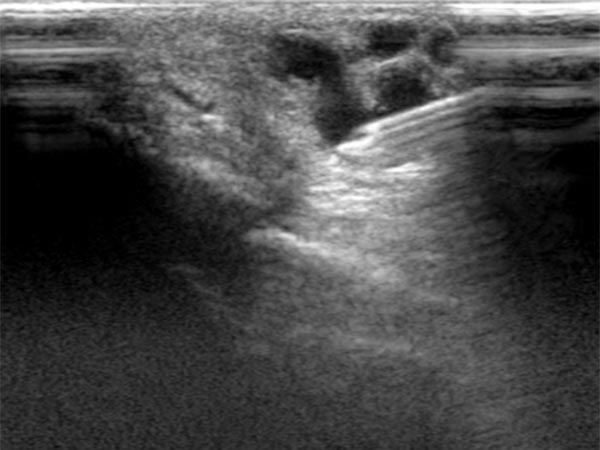

Percutaneous ultrasound-guided advancement of the puncture needle into the drainage vein of the digital AVM.

After embolization now clearly echogenic formations in the embolized vessel with dorsal acoustic shadowing due to the embolic agent after filling of the AVM nidus.